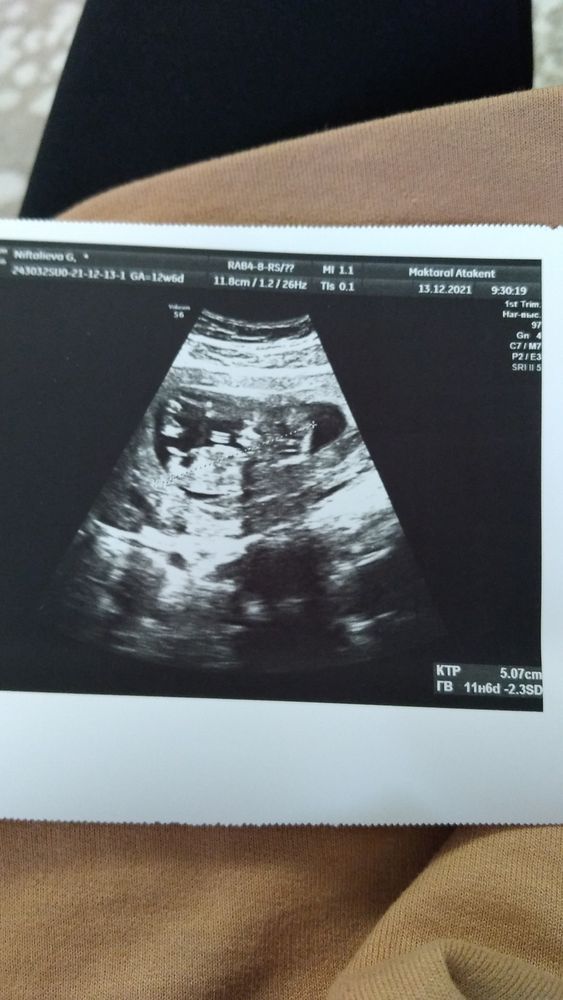

Всем привет. Была сегодня на первом скрининге. Все органы плода в норме по размерам. Только мочевой пузырь был увеличен 6.8 мм. Написала ре, жду когда ответит. А пока ответит решила посоветоваться с вами и заодно получить поддержки. Как думаете, это не опасно для малыша? Боюсь синдрома мегацистиса 😔

Посмотрела у своих зайчиков мочевой пузырь. Написано просто почти не видно/видно....тоже обалдеть можно от такого описания шикарного,думай что хочешь 😭

Алёна, я тут с одним то вся изпереживалась, с двумя вдвойне волнуешься за каждого. Спасибо вам за поддержку ❤ не говорите, в заключении пишут черт пойми что, а потом думай и не сп ночами 😬 кровь завтра сдавать буду. Я так волновалась и боялась что что то не то будет с сердечком или головой, оказалось бояться нужно совсем за другое. В последнее время многие жалуются на ошибки узи, так что думаю и мы с вами в их числе) не переживайте, с вашими детками все будет хорошо) скоро возьмем наших малышей на ручки и забудем все эти проблемы как страшный сон)